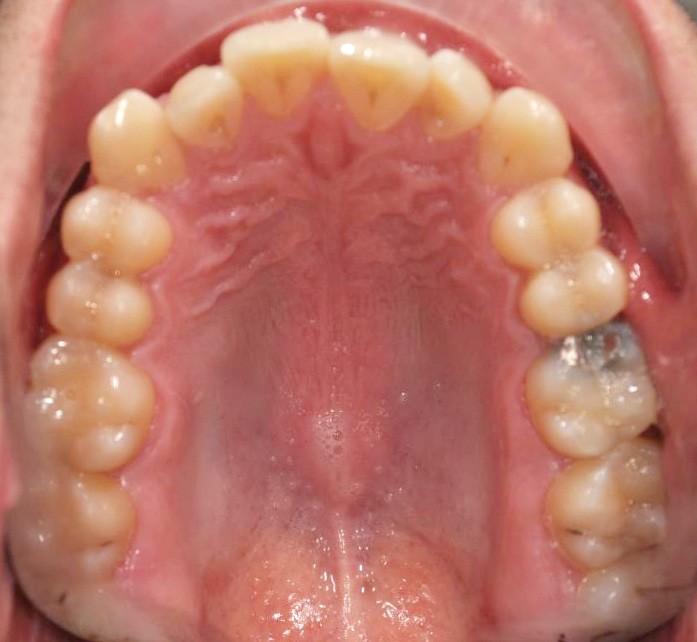

L’examen endobuccal

En intra-arcades (fig. 4-6), on note une classe III molaire et canine (fig. 4-5), trois plans d’occlusion, une déviation des milieux d’origine mandibulaire et un inversé articulé du bloc incisif maxillaire ; le biotype parodontal est fin, et l’on note des récessions gingivales (12, 13, 23, 33, 43) certainement dues à la mauvaise position et aux forces mal réparties lors de la mastication (fig. 5). L’arcade maxillaire est carrée avec une DDM antérieure (fig. 7), l’arcade mandibulaire étroite et allongée (fig. 8).